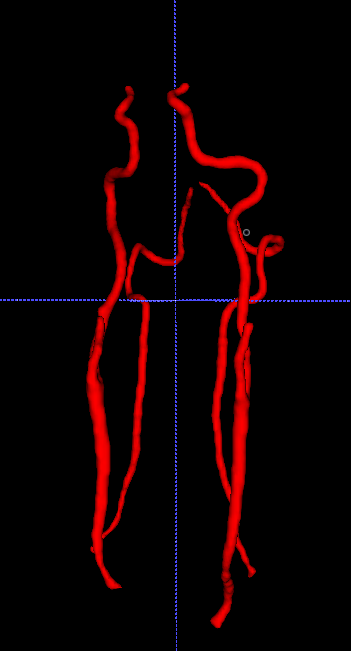

The backprojection operator causes a kind of shroud (Figure 3.1), so we have to think about a filtrated backprojection. Therefore, we apply a convolutional layer before backprojection. Using filters, which get adapted during training for each projection direction individually, leads to a more satisfying result (Figure 3.1).

\phantomcaption